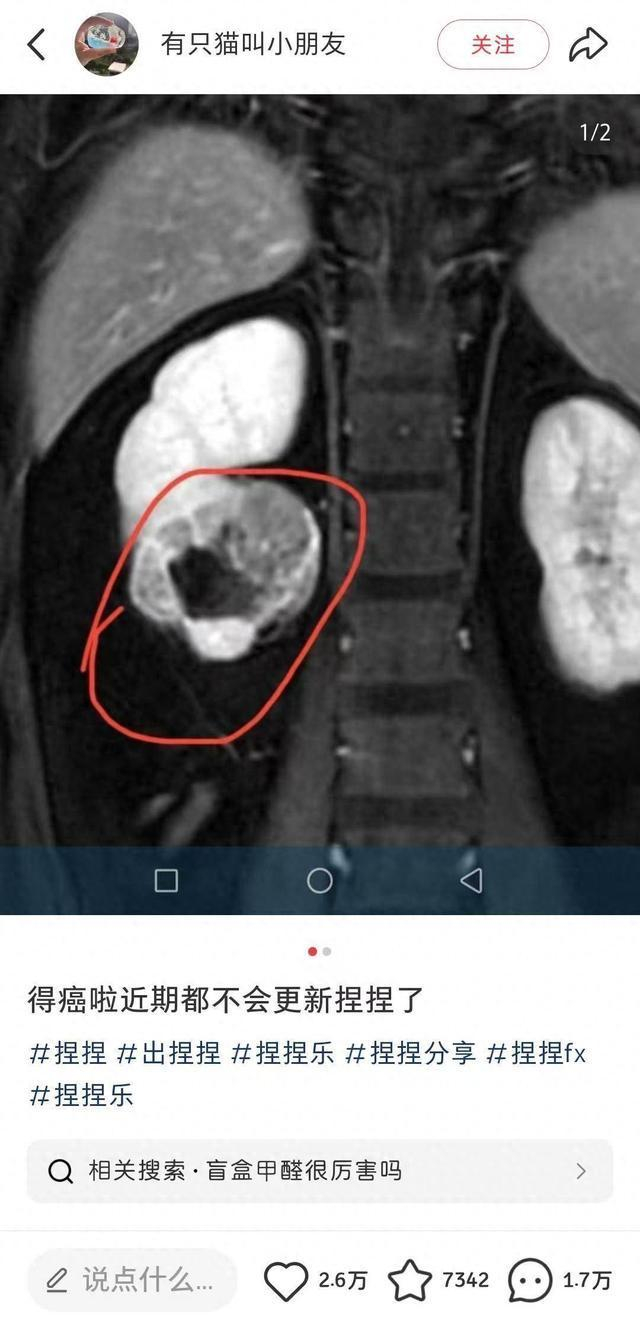

近日,一位ID名为“有只猫叫小朋友”的捏捏博主发文告诉粉丝:

“得癌了,近期都不会更新捏捏了。”

博主公开了自己的诊断病例,显示诊断意见为“右肾下级占位,肾ca可能,建议穿刺活检。”

意味着医院给出的诊断是右肾下极区域出现异常组织占据,存在肾细胞癌的可能。